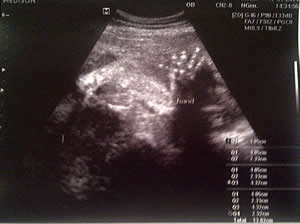

The 7-month (6 months 2 and a half weeks to be exact) scan image above shows a healthy baby of just over 1kg; 800g+ being a healthy weight.

The doctor was very pleased with the health of my wife, too, and said she had good blood pressure and healthy lungs.

My wife was 35 when she gave birth. Our baby girl was born at a healthy 8lbs. She loves music too. I’ll take credit for that!